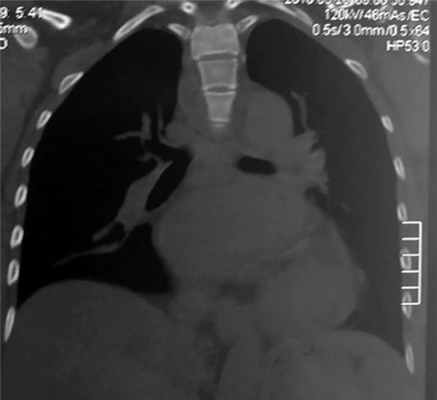

КТ органов грудной клетки: новообразование среднего средостения, кaрдиомегaлия (рис. 1).

Рис. 1. КТ органов грудной клетки. Новообразование средостения.

КТ органов грудной клетки от 28.03.2016: в среднем средостении определяется инфильтрация тканей, трахея несколько оттеснена вправо. В легких без очaгово-инфильтрaтивных изменений. Легочный рисунок прослеживается по всем полям, усилен по мелкоячеистому типу. Лимфоузлы средостения не увеличены. Сердце расширено за счет левых отделов, тени аортального протеза и аннулопластического кольца митрального клапана (рис. 6).

Рис. 6. Послеоперационная КТ органов грудной клетки.